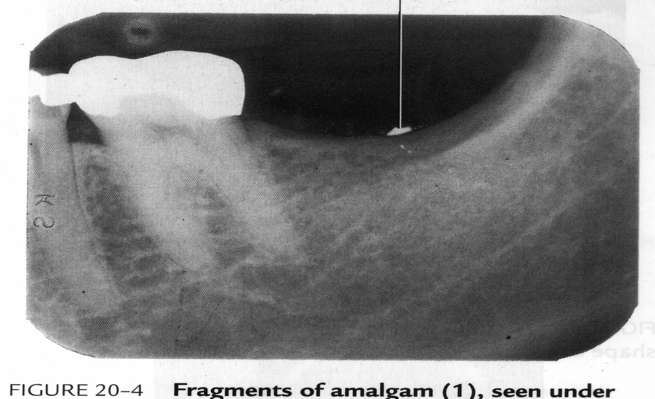

Amalgam